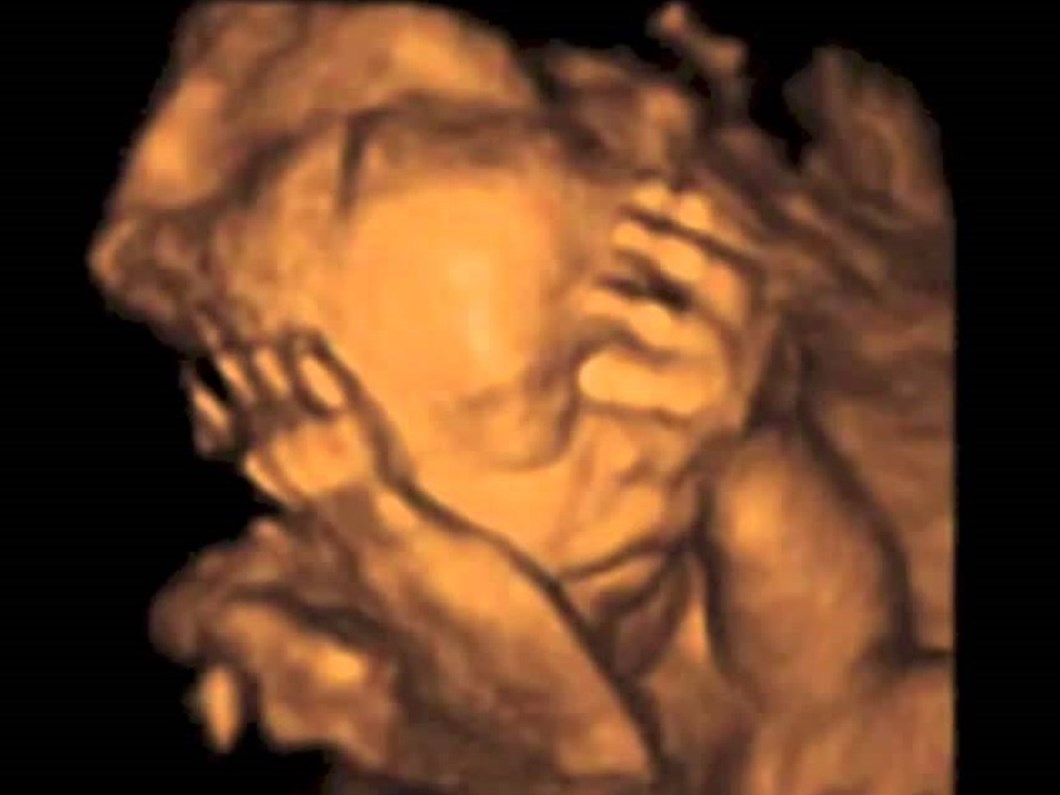

bebekte su toplanmasi ultrason klinik

bebeklerde hidrosefali ve mikrosefali nedir anne karninda bebegin beyninde su toplamasi bebeklerde hidrosefali ve mikrosefali nedir anne karninda bebegin beyninde su toplamasi haberinpesinde com urfa haber sitesi urfa haber